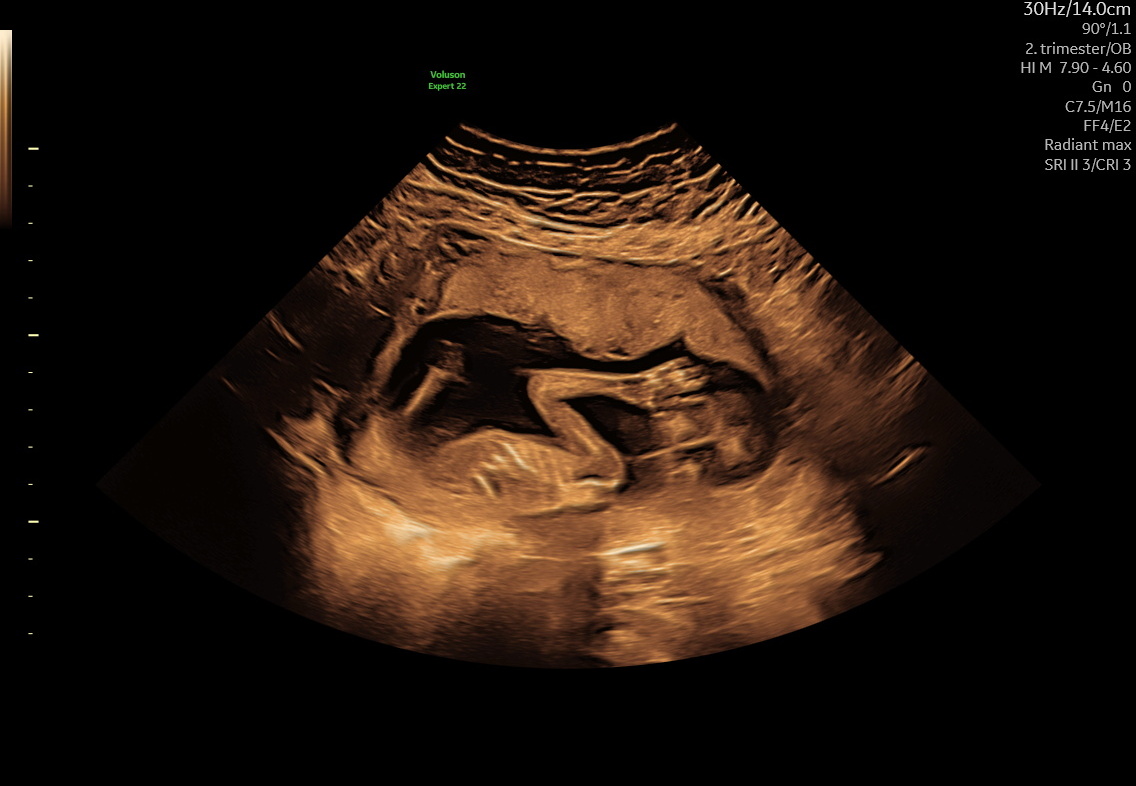

Tryghedsscanning

Hjertelyd og trivsel fra uge 14+0

445 kr. / 395 kr. returkunde